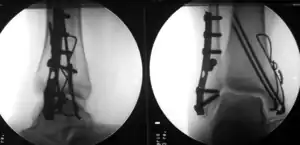

Treatment

The broad goals of treating ankle fractures are restoring the ankle joint to normal alignment, healing the fracture, and preventing arthritis.[9] The stability of the ankle joint often dictates treatment. Certain fracture patterns are stable and are thus treated without surgery similarly to ankle sprains. Unstable fractures require surgery, most often an open reduction and internal fixation (ORIF), which is usually performed with permanently implanted metal hardware that holds the bones in place while the natural healing process occurs. A cast or splint will be required to immobilize the ankle following surgery.[12] Stable ankle fractures with preserved joint alignment may be treated with non-operative measures (splinting, casting, and/or walking boot).[12]

After surgery for a broken ankle, it is common practice for people to be told to keep weight off their ankle for 6 weeks (delayed weight bearing). However, some surgeons encourage people to walk again after 2 weeks (early weight bearing). A randomised trial compared the safety of walking after 2 weeks with waiting 6 weeks. Researchers found that 4 months after surgery, people in both groups had similar ankle function (including pain, stiffness, and walking ability) and a similar number of complications. Costs to the NHS were lower for early weight bearing.[16][17]